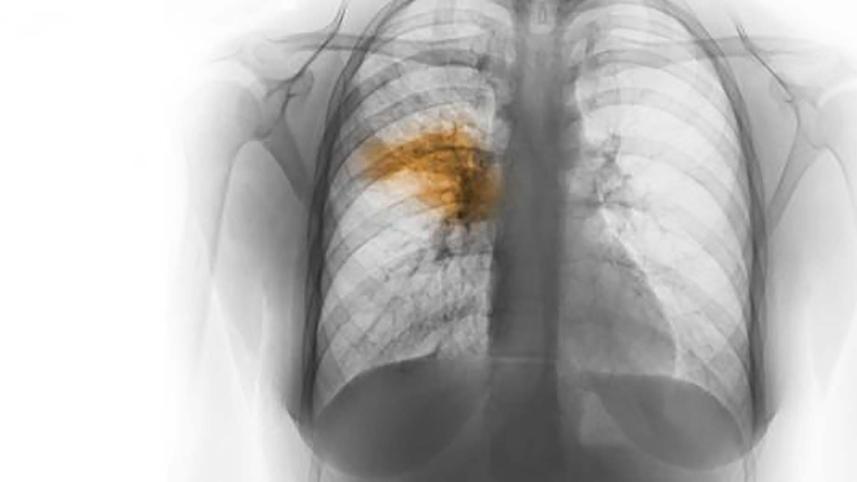

15 children die of pneumonia at CHT hospitals in 2 weeks

Fifteen children died of pneumonia at hospitals in Khagrachhari, Rangamati and Bandarban in the last two weeks, said doctors.